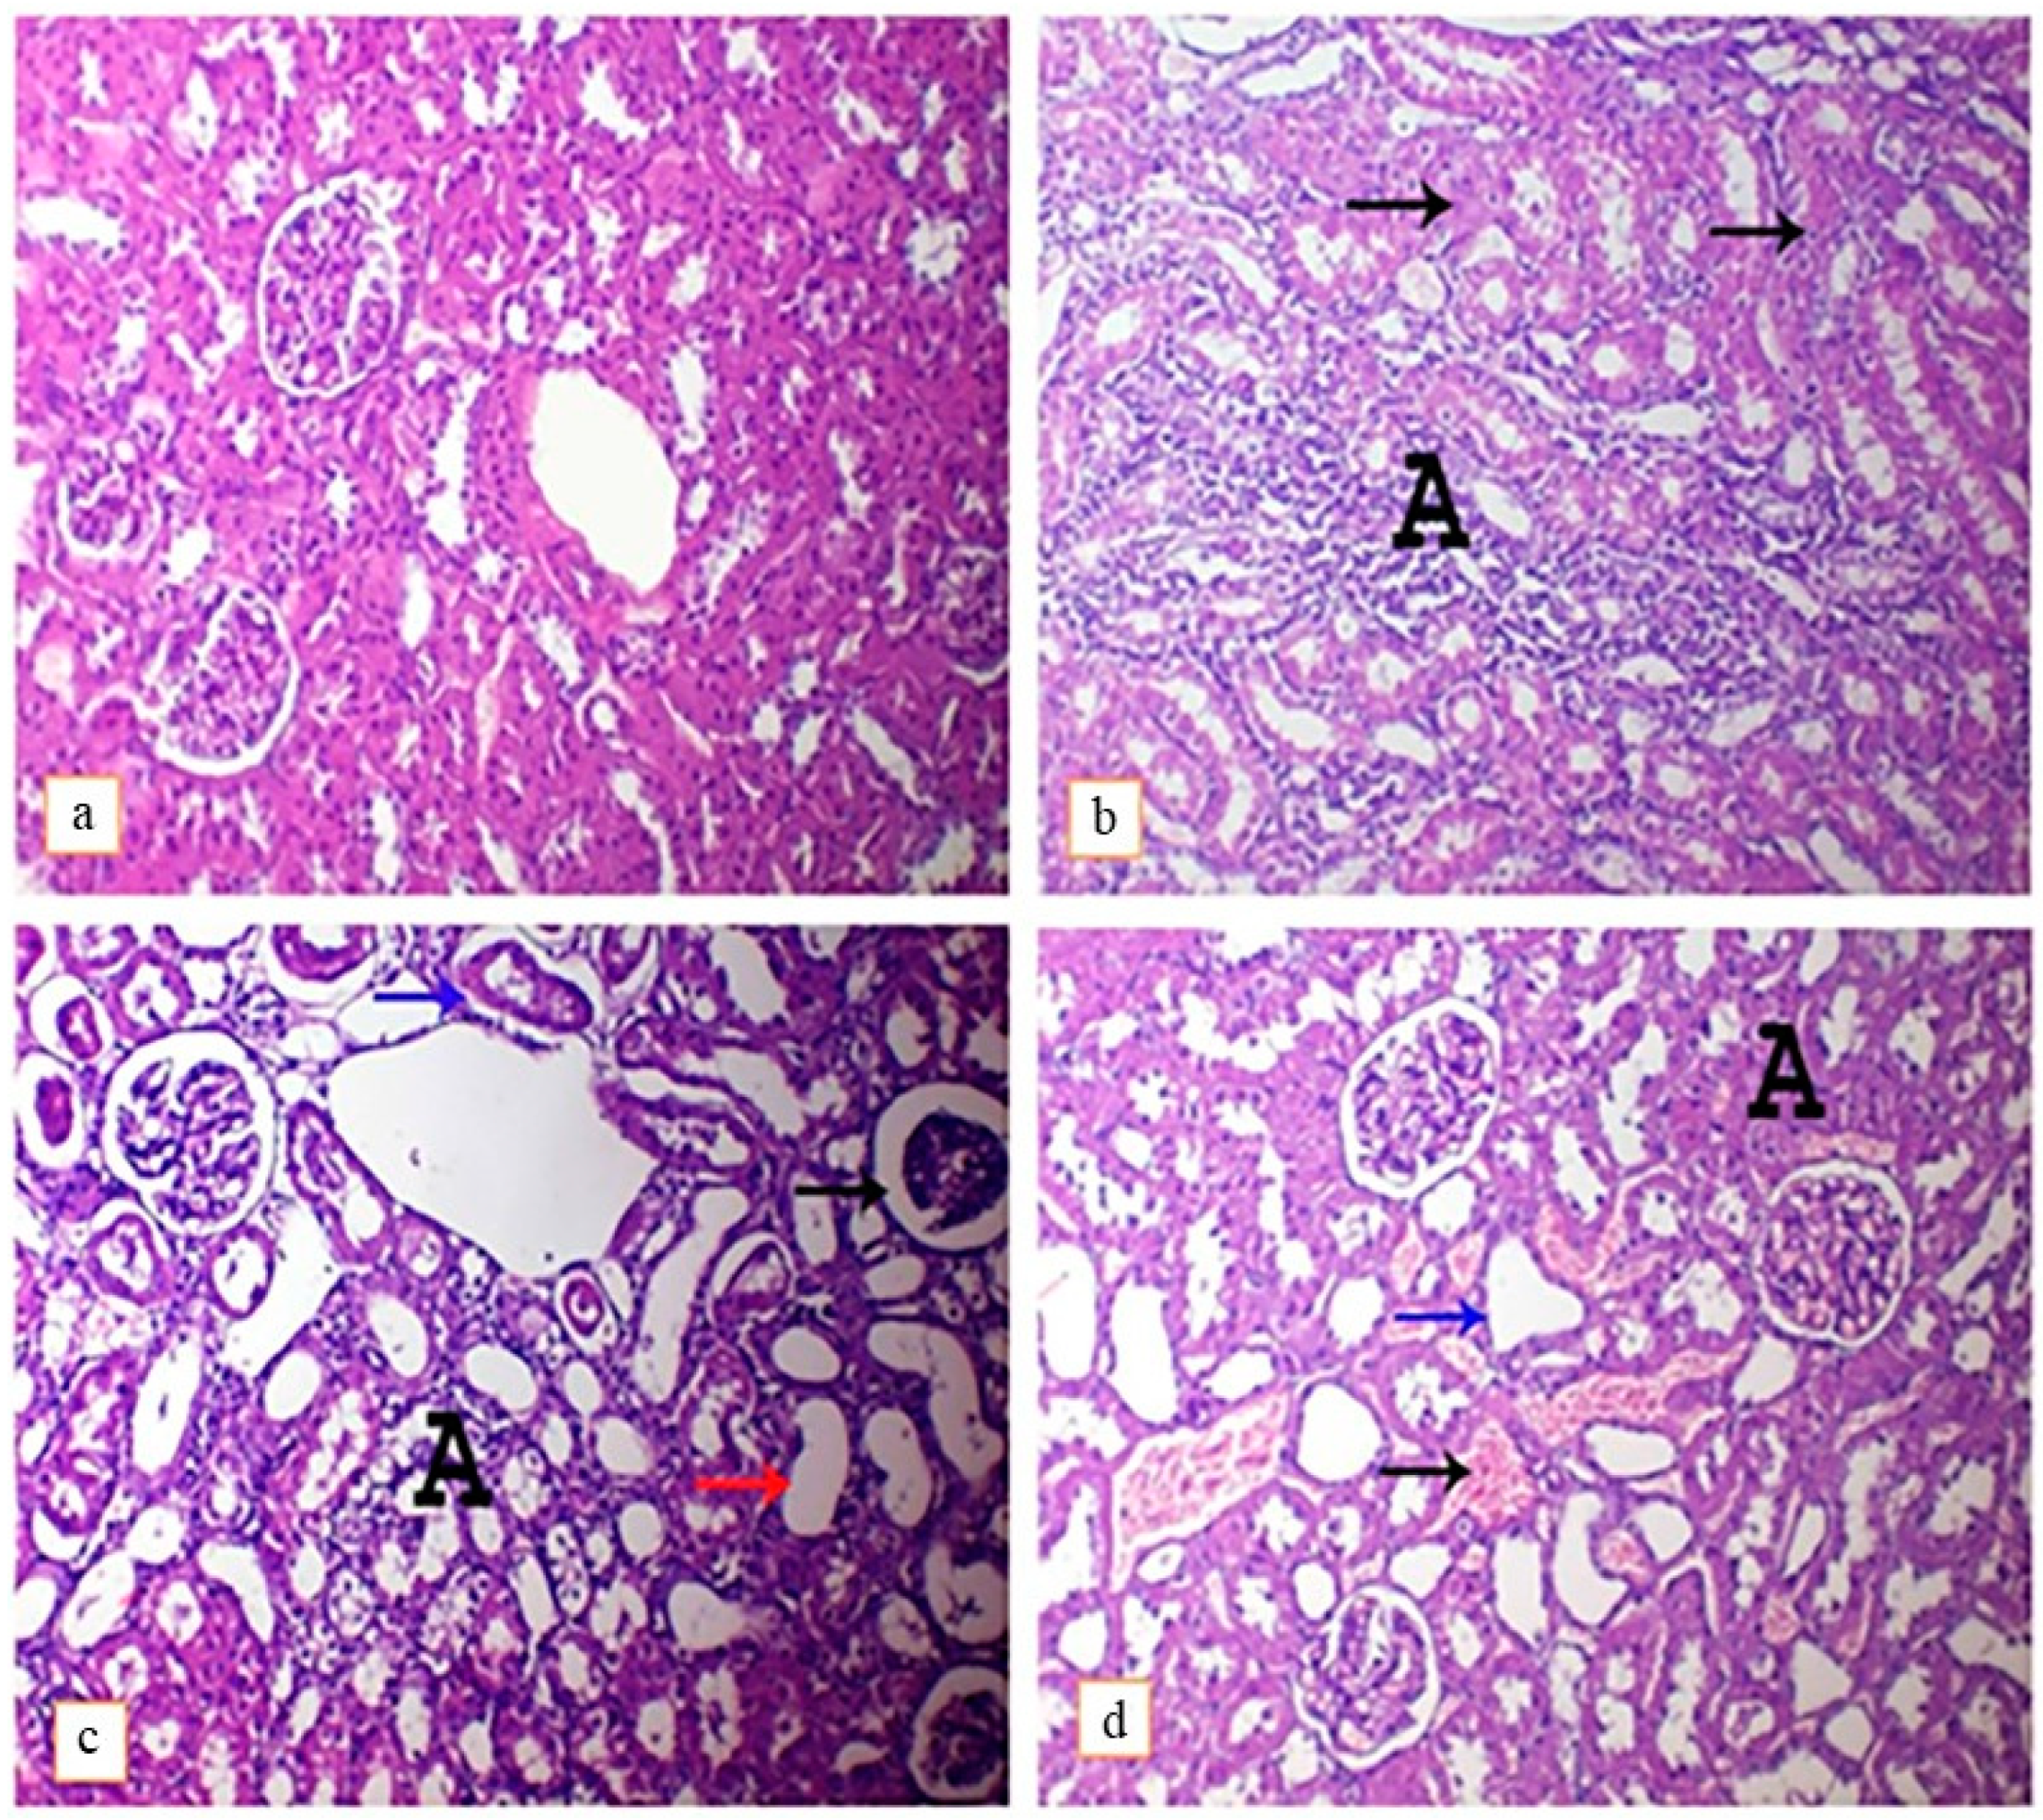

3.4.2. Kidney

| Incidence 1 and Severity 2 of Histopathological Lesions | ||||||||

|---|---|---|---|---|---|---|---|---|

| DEHP Intoxicated Rats | DEHP and Lutein-Treated Rats | |||||||

| Absent (-) | Mild (+) | Moderate (++) | Severe (+++) | Absent (−) | Mild (+) | Moderate (++) | Severe (+++) | |

| Liver | ||||||||

| 1-Hydropic degeneration | 0 | 2 | 0 | 5 | 3 | 1 | 2 | 1 |

| 2-Congested sinusoids | 2 | 2 | 2 | 1 | 5 | 2 | 0 | 0 |

| 3-Congestion of blood vessels | 1 | 2 | 2 | 2 | 2 | 2 | 1 | 2 |

| 4-Perivascular infiltration of inflammatory cells | 3 | 1 | 2 | 1 | 3 | 2 | 1 | 1 |

| 4-Necrotic foci | 1 | 3 | 1 | 2 | 3 | 4 | 0 | 0 |

| 5-Hemorrhage | 2 | 1 | 2 | 2 | 6 | 0 | 1 | 0 |